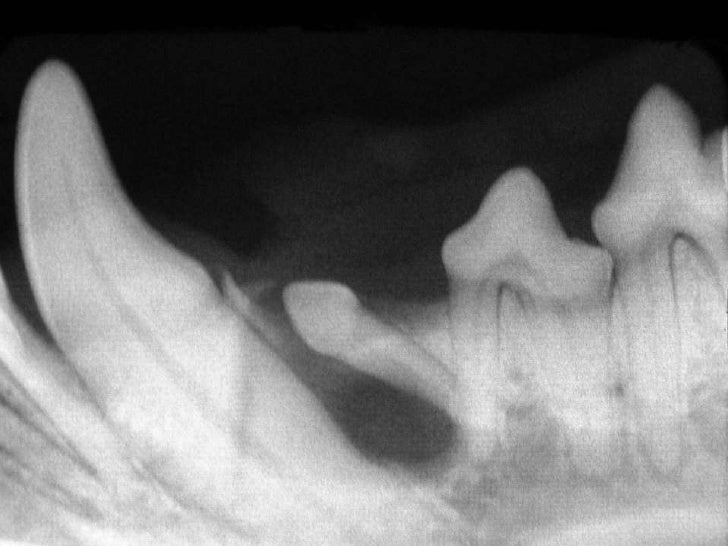

Veterinary Dentistry Surgical Extractions in the Dog and Cat Veterinary Dentistry Extractions Simple extractions involve the removal of single rooted teeth or the removal of teeth with multiple roots that have been sectioned. In the cat and dog, the routine technique for extraction is to loosen (luxate) and extract (elevation) each tooth root individually. Dog tooth extractions are commonly performed to remove diseased and painful teeth that develop due to various underlying. Veterinary Dentistry Extractions.